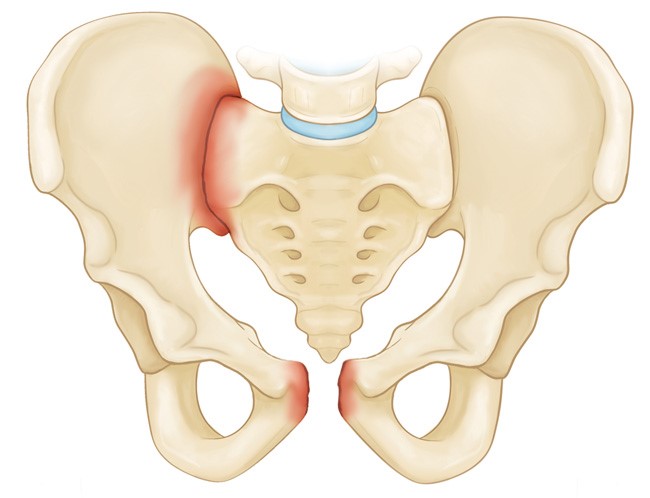

Таз – это не одна кость, как могло казаться многим. Он состоит из трех частей, крепко соединенных друг с другом. Строение таза учитывается в постановке диагноза, определении вида перелома, ведь часто повреждается только одна кость.

В состав тазового кольца входят три парные кости:

- изолированные — переломы лобковых, седалищных или подвздошных костей, как правило, называют стабильными. Под действием травмирующей силы происходит перелом наиболее выступающих частей: гребней или крыльев подвздошной кости, бугров седалищной, ветвей лобковой;

- нестабильные переломы сопровождаются нарушениями тазового кольца. В большинстве случаев травмируются внутренние органы. В зависимости от локализации повреждения различают вертикально нестабильные переломы, когда смещение происходит в вертикальной плоскости. Ротационные переломы характеризуются горизонтальным смещением отломков;

- повреждения вертлюжной впадины. Перелом тазобедренной кости возникает вследствие нарушения целостности дна или краев суставной поверхности впадины.

- сочетанная травма: переломы костей таза сопровождаются вывихами в лонном или крестцово-подвздовшном сочленении.

Переломы подвздошной кости

При повреждении подвздошной кости наблюдается укорочение конечности, боль в области крыла или гребня с соответствующей стороны. Существует специфический симптом задней ходы, когда пациенту легче передвигаться спиной вперед.

Переломы лобковой кости

Чаще при этом виде травм тазовое кольцо не нарушено. Пациент занимает вынужденное положение, при котором боль уменьшается: лежа на спине, ноги согнуты в коленных суставах, разведены в сторону. Для наглядности поза человека при переломах таза (поза лягушки) показана на фото.

Переломы седалищной кости

Повреждение возникает при падении на таз, чаще зимой или же во время занятий спортом. Пациент жалуется на острую боль, отек, покраснение на ягодицах.

Переломы с нарушением целостности тазового кольца

Переломы костей таза с нарушением целостности переднего и заднего полуколец характеризуются патологической подвижностью при незначительном надавливании на таз, асимметрией. Болевой синдром выражен сильно, приводит к потере сознания. На коже наблюдаются кровоподтеки, синяки.